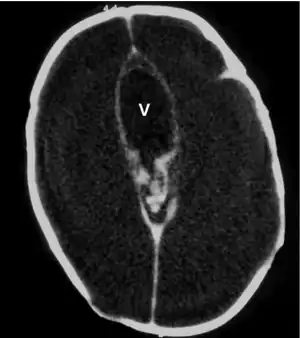

Hydrocephalus

Noncommunicating

Communicating

Treatment varies depending on whether or not it occurs with other medical conditions in the child and where cerebrospinal fluid is present.[12] If benign and found between the brain and skull then no surgery is needed.[12][13] If excess fluid is found between the ventricle spaces in the brain then surgery will be needed.[13]